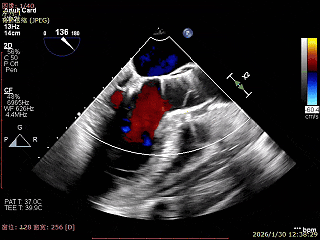

LVOT切面可见主瓣二尖瓣术后反流基本消失